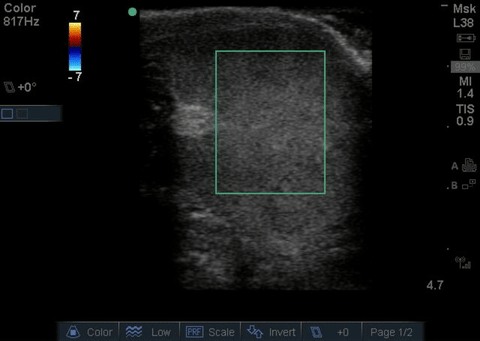

Absent testicular blood flow

| current | 13:57, 15 August 2016 | 480 × 341 (1.13 MB) | Neil.m.young (talk | contribs) | Absent testicular blood flow |